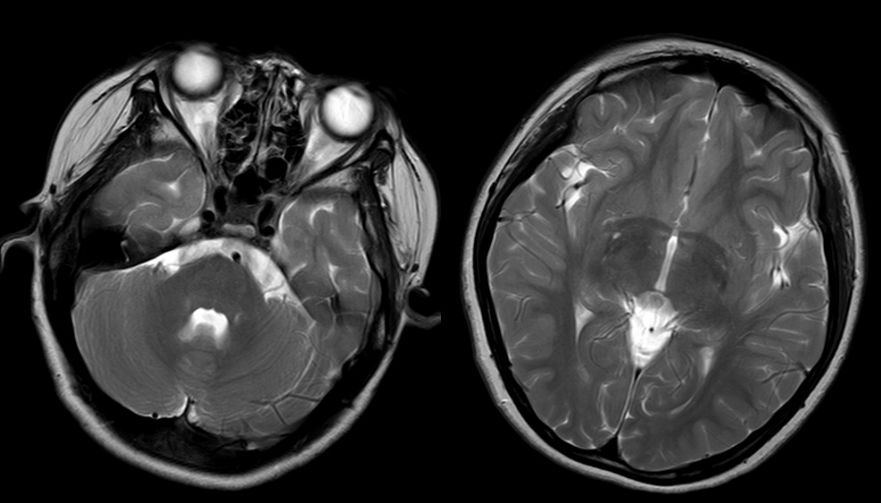

头颅MR:左侧小脑半球异常信号,左侧脑室体部后外侧异常信号,双侧半卵圆中心、侧脑室旁血管周围间隙增多。颈胸髓及腰骶部MRI提示:C3-T4平面脊髓肿胀,伴多发异常信号,胸髓全段肿胀,伴信号异常,腰骶髓异常信号影,考虑脊髓炎可能(图1)。

图1. 第一次住院头颅及脊髓MRI,显示左侧小脑半球异常信号。脊髓全段肿胀,伴信号异常,腰骶髓异常信号影,考虑脊髓炎可能。